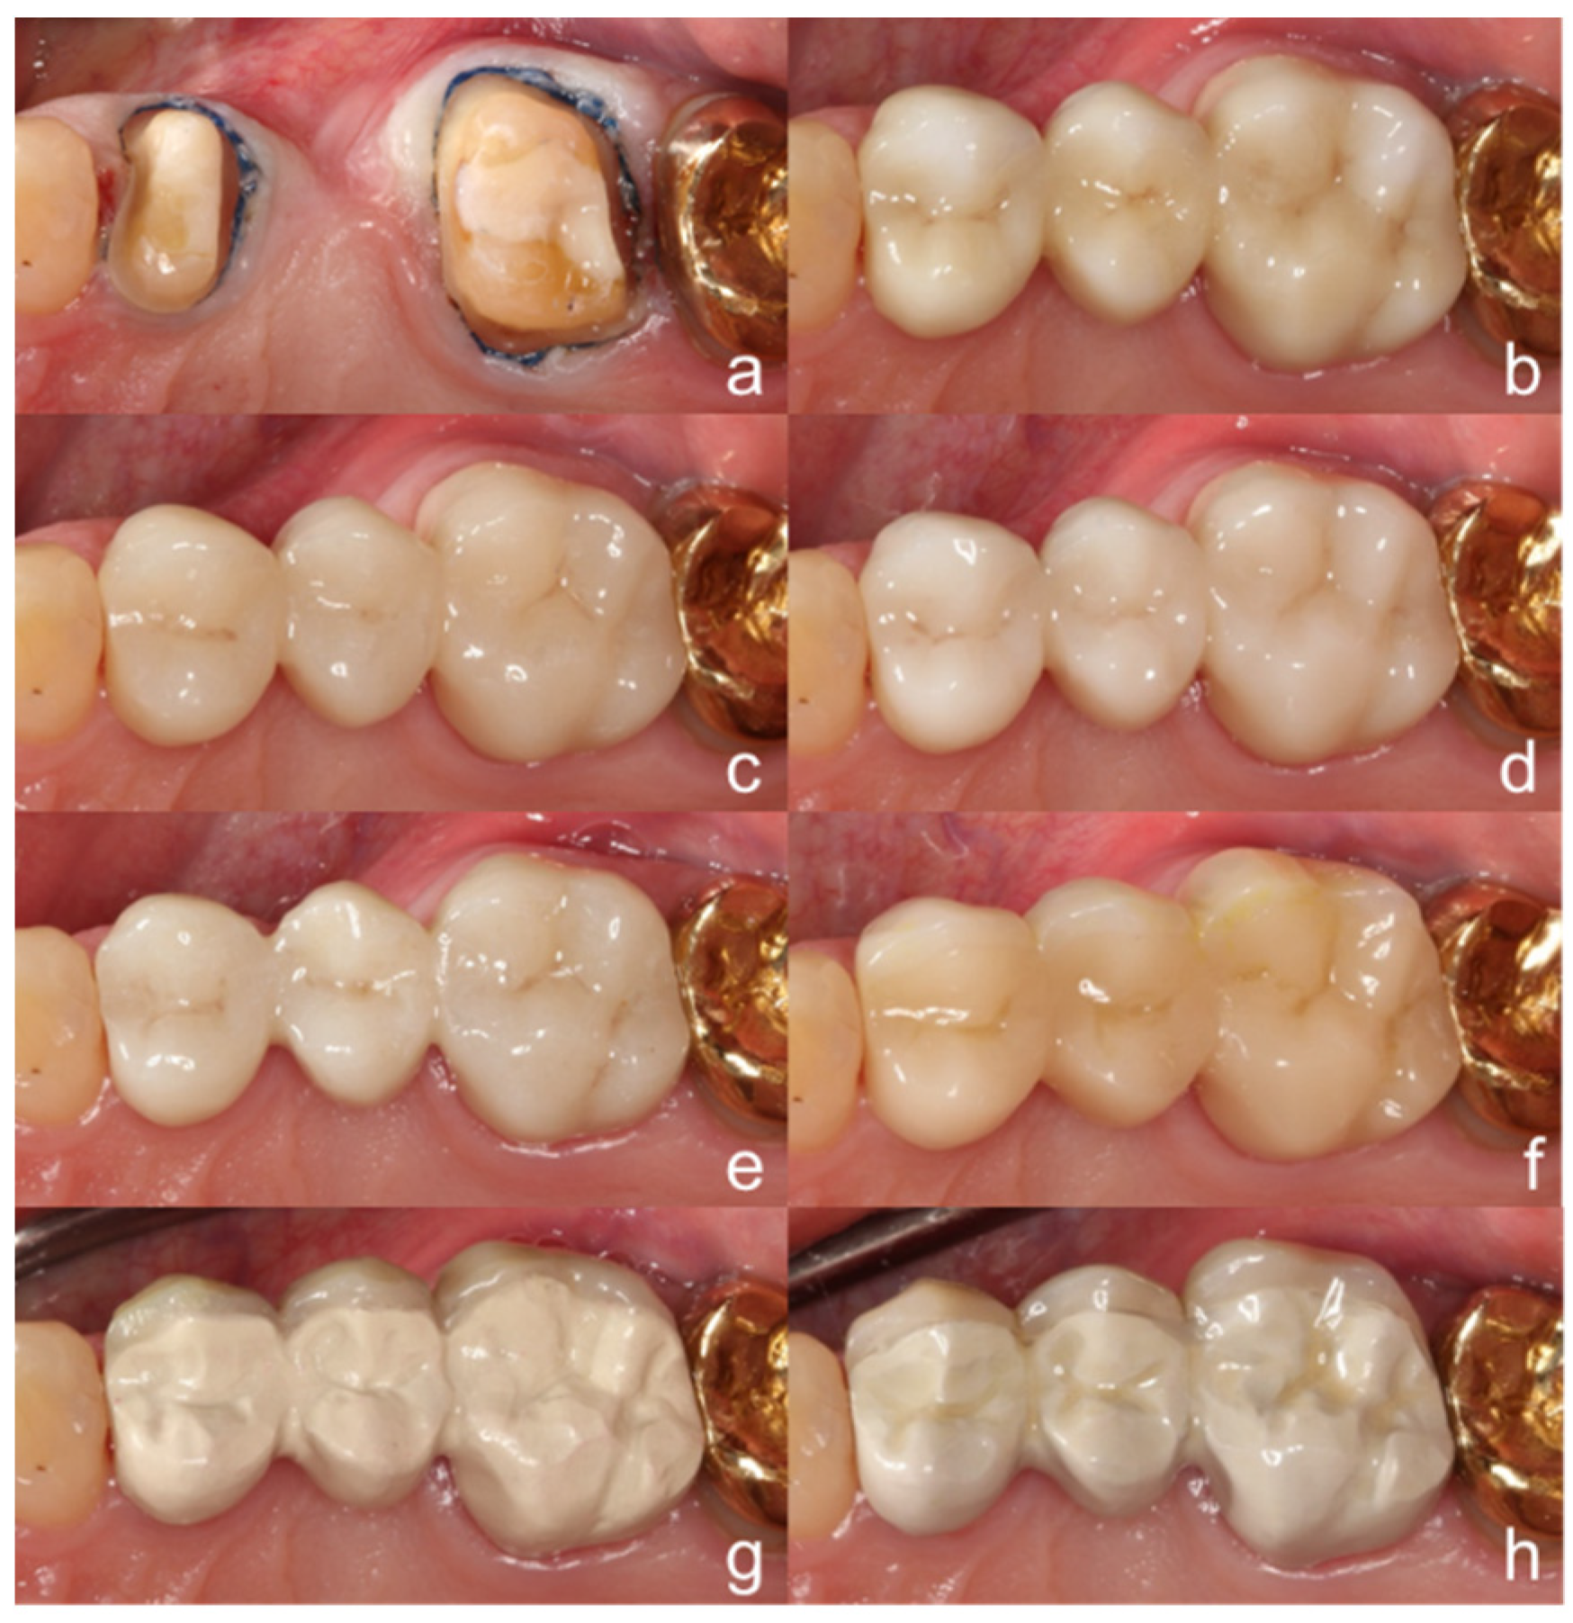

2. Materials and Methods

3. Results